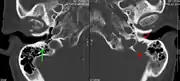

- A CT of the brain revealed a lytic lesion in the left temporal bone (right side of image), and petrous temporal bones involving the mastoid segment of the facial nerve canal. Red arrows: lesion; green arrow: normal contralateral facial nerve canal. The lesions are consistent with a myeloma deposit.